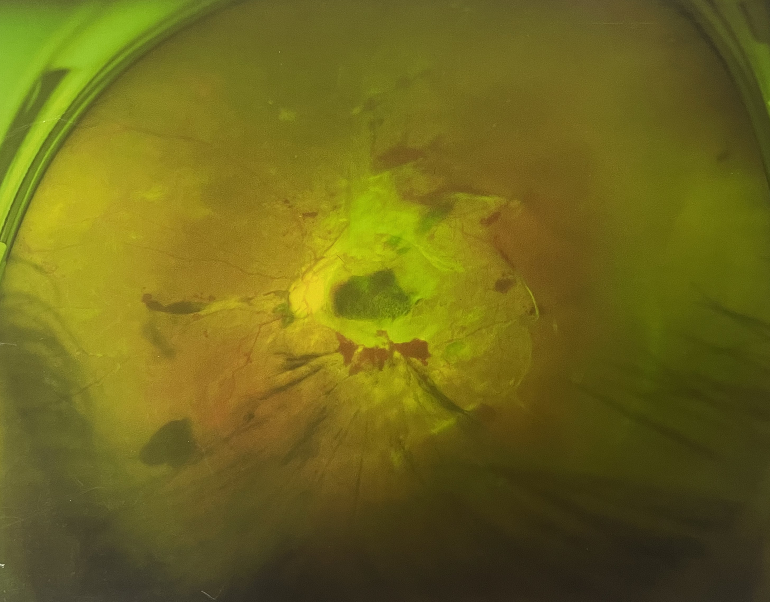

右眼術(shù)后

4個月前的左眼

左眼發(fā)展到糖尿病視網(wǎng)膜病變VI期

由于王女士的左眼沒有聽從醫(yī)生盡快做手術(shù)的建議,一直耽誤,從4月前的0.4視力逐漸下降到僅剩眼前手動,導(dǎo)致左眼發(fā)展到糖尿病視網(wǎng)膜病變VI期(屬于6期糖網(wǎng)中的晚期),已經(jīng)產(chǎn)生大量新生血管+纖維增值+廣泛牽拉性視網(wǎng)膜脫離,由于耽誤了病情,且病情發(fā)展異常迅速,導(dǎo)致目前左眼連保住眼球都很困難。

“而如果4月余前,左眼及時手術(shù)(當(dāng)時左眼病情比右眼輕,增殖膜還未累及黃斑),左眼將恢復(fù)的比右眼還好,甚至可以恢復(fù)到0.8或1.0,而現(xiàn)在連保住眼球的機(jī)會都很渺茫”,張小虎醫(yī)生表示實在可惜。